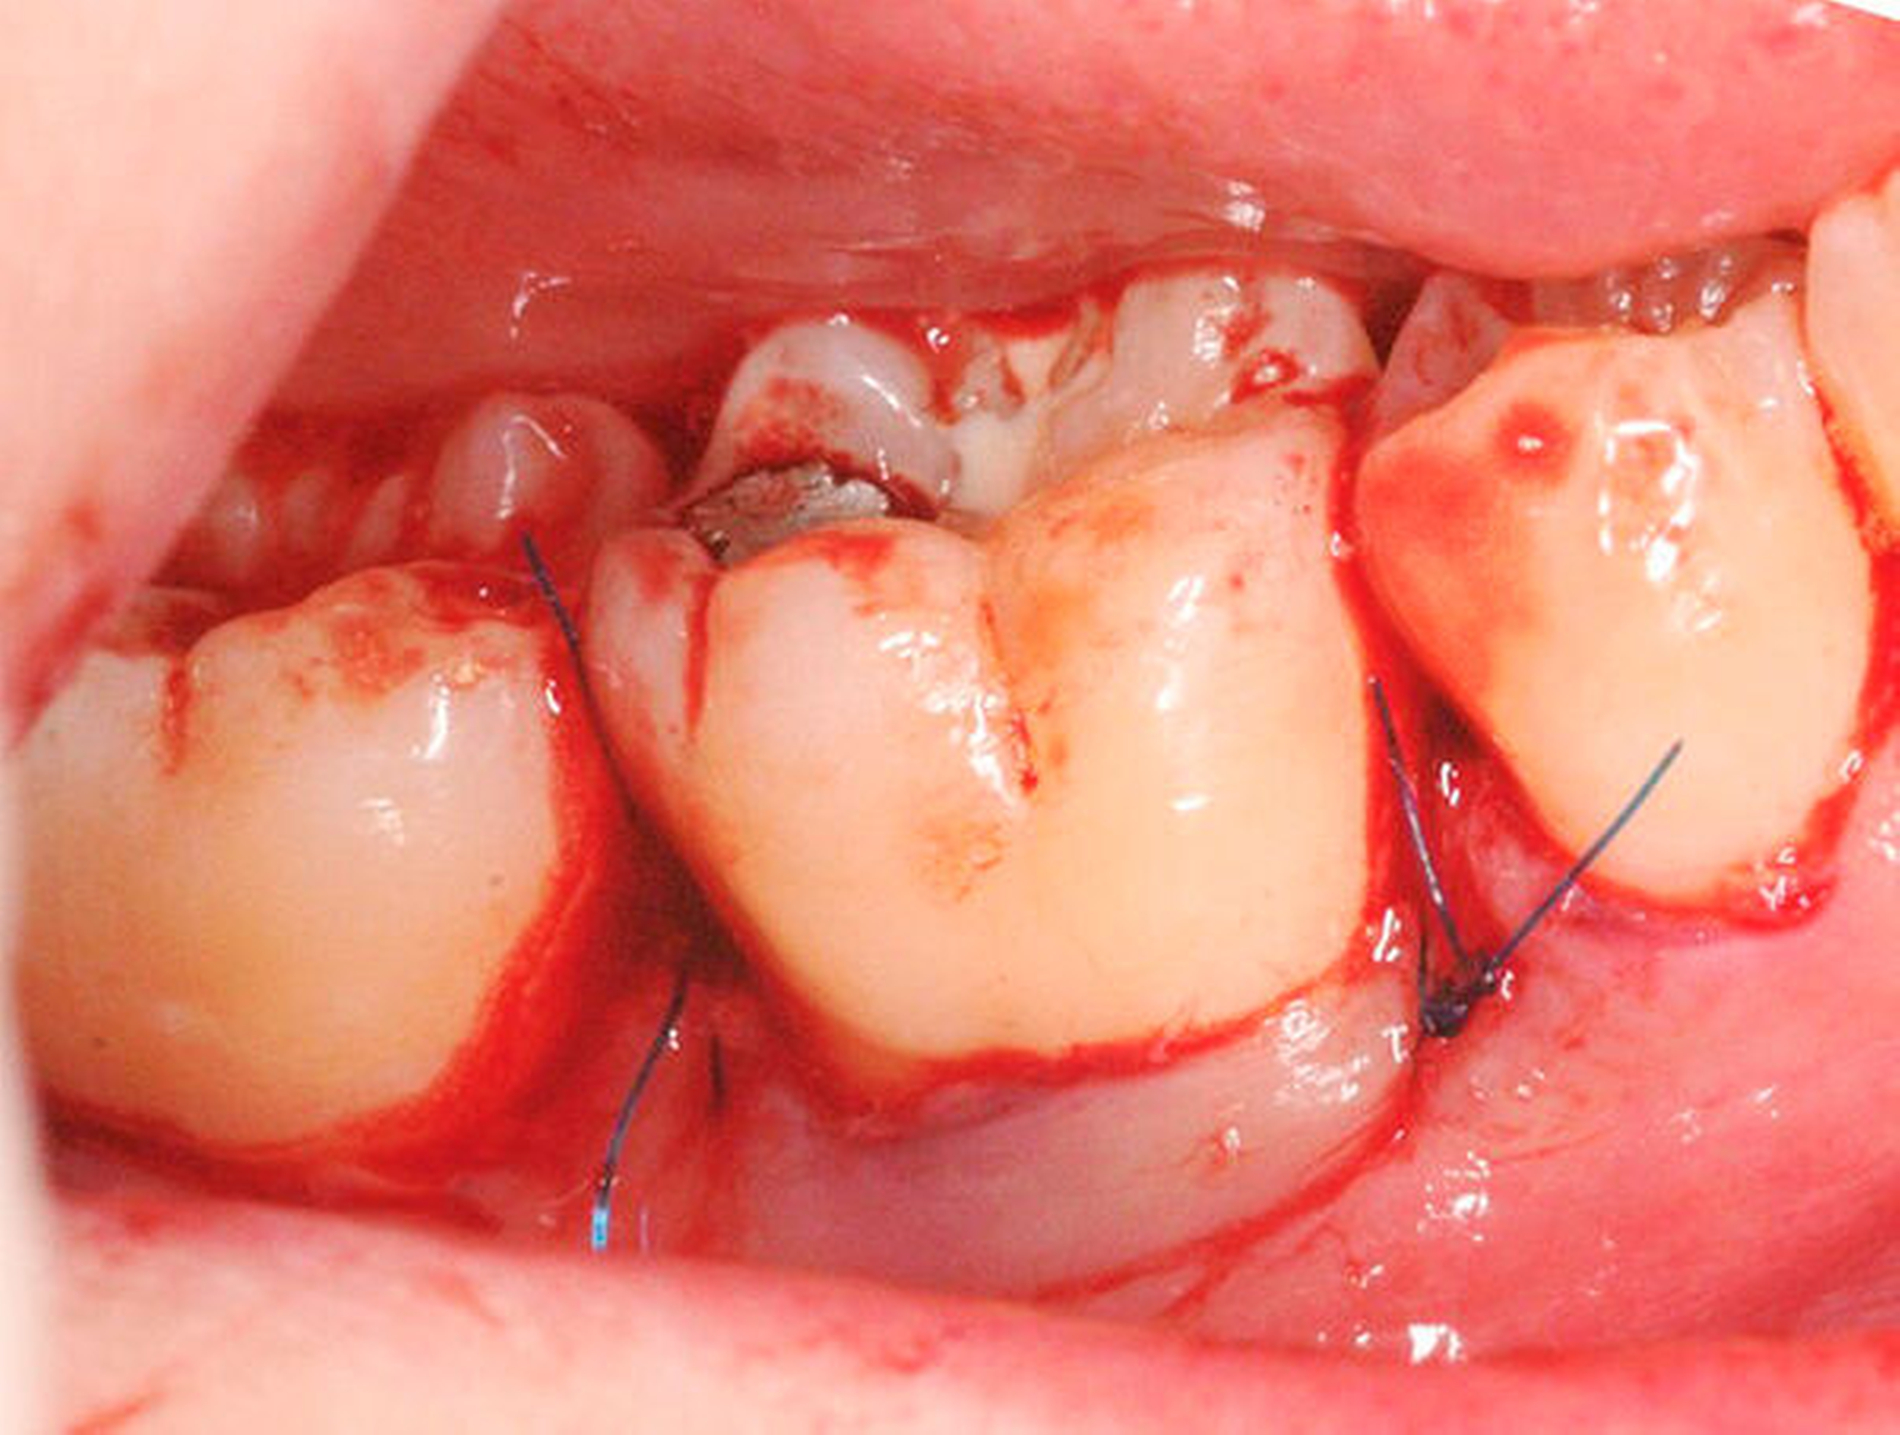

Diese Fragestellung in der Leitlinie widmet sich dem Vergleich der Ergebnisse nach Lappenoperation mittels Zugangslappen (Abbildung 3), also Lappenbildung ohne gezielten Gewebsverlust, und resektiver Parodontalchirurgie – mit gezieltem Gewebsverlust, jedoch ohne zusätzliche Materialien zur parodontalen Regeneration [Polak et al., 2020]. Dabei werden alle chirurgischen Verfahren mit Resttaschen ab 5 mm nach vorheriger subgingivaler Instrumentierung verglichen. Bei der Betrachtung werden MWF (Abbildung 1), Excisional New Attachment Procedure (ENAP) in der Gruppe der Zugangslappen geführt. Die Gruppe der resektiven Parodontalchirurgie besteht aus auch zum Teil älteren Verfahren mit deutlicher Veränderung der Gingiva- und der Knochenkontur.

Den evidenzbasierten Empfehlungen der klinischen Leitlinie zu regenerativer Therapie von Knochentaschen (Abbildung 4) liegen 22 RCTs mit 1.182 Zähnen bei 1.000 Patienten zugrunde [Nibali et al., 2020]. In der Mehrzahl der Studien führte die regenerative Parodontaltherapie zu besseren parodontalen Parametern (höherer CAL-Gewinn und flachere Taschen) im Vergleich zur Instrumentierung unter Sicht (Zugangslappenoperation). Für den CAL-Gewinn wurde ein zusätzlicher Nutzen von durchschnittlich 1,34 mm (95 Prozent-KI: [0,95; 1,73]) und für die TST-Reduktion von 1,20 mm (95 Prozent-KI: [0,85; 1,55]) beobachtet. Das stellt eine Verbesserung von 80 Prozent (95 Prozent-KI: [60 Prozent; 100 Prozent]) im Vergleich zu den Kontrollgruppen dar. Ein mittlerer Unterschied in dieser Größenordnung wird als klinisch relevant erachtet, da damit das Risiko des Zahnverlusts reduziert wird. Beobachtungsstudien und experimentelle Studien, die sich mit Zahnüberlebensraten von 3 bis 20 Jahren beschäftigt haben, zeigten bessere Überlebensraten von Zähnen mit parodontaler Regeneration in regelmäßiger unterstützender Parodontaltherapie [Stavropoulos et al., 2021].

Was ist das adäquate Lappendesign für die regenerative Therapie von Resttaschen im Bereich von Knochentaschen?

Dieser Empfehlung liegen zwei systematische Übersichtsarbeiten zugrunde [Graziani et al., 2012; Nibali et al., 2020]. Durch einen Papillenerhaltungslappen lassen sich höhere CAL-Gewinne und TST-Reduktionen erreichen. Im Vergleich zur Instrumentierung unter Sicht (Zugangslappenoperation) führt diese Technik zu geringeren postoperativen Rezessionen. Die erhöhte Komplexität dieser Methode bedarf allerdings zusätzlichen Trainings. (Abbildung 4).